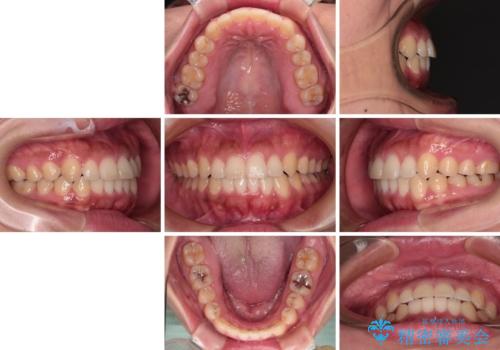

【モニター】カリエール・ディスタライザーを併用した八重歯のインビザライン矯正

カリエールディスタライザーを併用したことで、すっきりとした口元になり、上下の正中を合わせることができました。